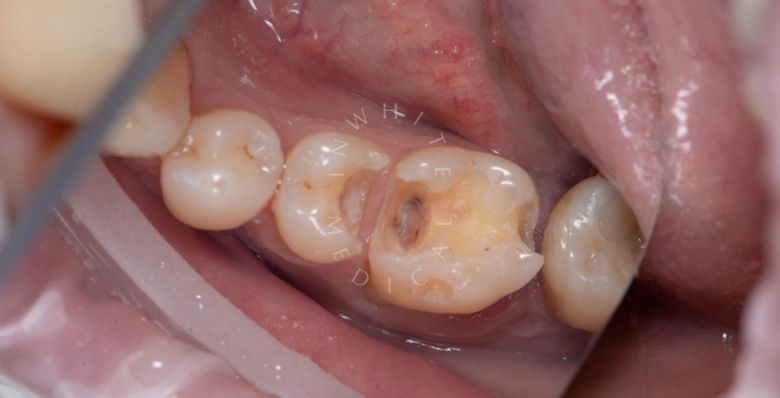

Художественная реставрация формы зубов

Стоматология Москва лучшие клиники. Художественная реставрация формы зубов - до процедуры